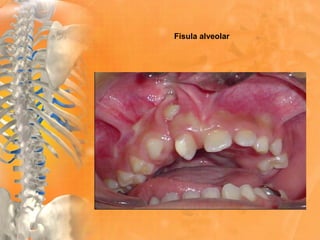

Fisula alveolar

Fractura